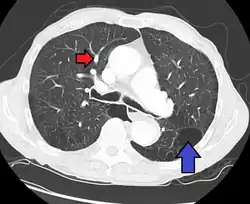

Uma avaliação diagnostica completa inclui uma historia, exame físico, radiografia de tórax, provas de função pulmonar, eletrocardiograma (ECG), ecocardiograma, imageamento de ventilação perfusão e cateterismo cardíaco. Em alguns casos, pode ser necessária uma biopsia pulmonar, realizada por toracoscopia, visando elaborar um diagnóstico definitivo. O cateterismo cardíaco do lado direito do coração revela a pressão arterial pulmonar elevada. Um ecocardiograma pode avaliar a progressão da doença e excluir outras condições com sinais e sintomas similares.